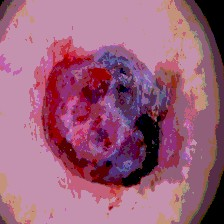

Timely identification and treatment of rapidly progressing skin cancers can significantly contribute to the preservation of patients' health and well-being. Dermoscopy, a dependable and accessible tool, plays a pivotal role in the initial stages of skin cancer detection. Consequently, the effective processing of digital dermoscopy images holds significant importance in elevating the accuracy of skin cancer diagnoses. Multilevel thresholding is a key tool in medical imaging that extracts objects within the image to facilitate its analysis. In this paper, an enhanced version of the Mud Ring Algorithm hybridized with the Whale Optimization Algorithm, named WMRA, is proposed. The proposed approach utilizes bubble-net attack and mud ring strategy to overcome stagnation in local optima and obtain optimal thresholds. The experimental results show that WMRA is powerful against a cluster of recent methods in terms of fitness, Peak Signal to Noise Ratio (PSNR), and Mean Square Error (MSE).